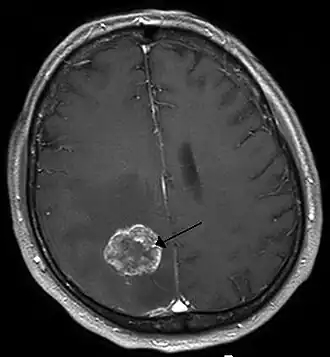

| Ressonância magnética de metástases de um cancro do pulmão no hemisfério cerebral direito . | |

Os tumores do cérebro secundários, ou metástases, são mais comuns que os tumores do cérebro primários.[2] Cerca de metade das metástases são provenientes do cancro do pulmão.[2] Os tumores cerebrais primários afetam por ano cerca de 250 000 pessoas em todo o mundo, o que corresponde a menos de 2% do total de casos de cancro.[3] Em jovens com idade inferior a 15 anos, os tumores do cérebro são a segunda principal causa de cancro, atrás apenas da leucemia linfoide aguda.[8]